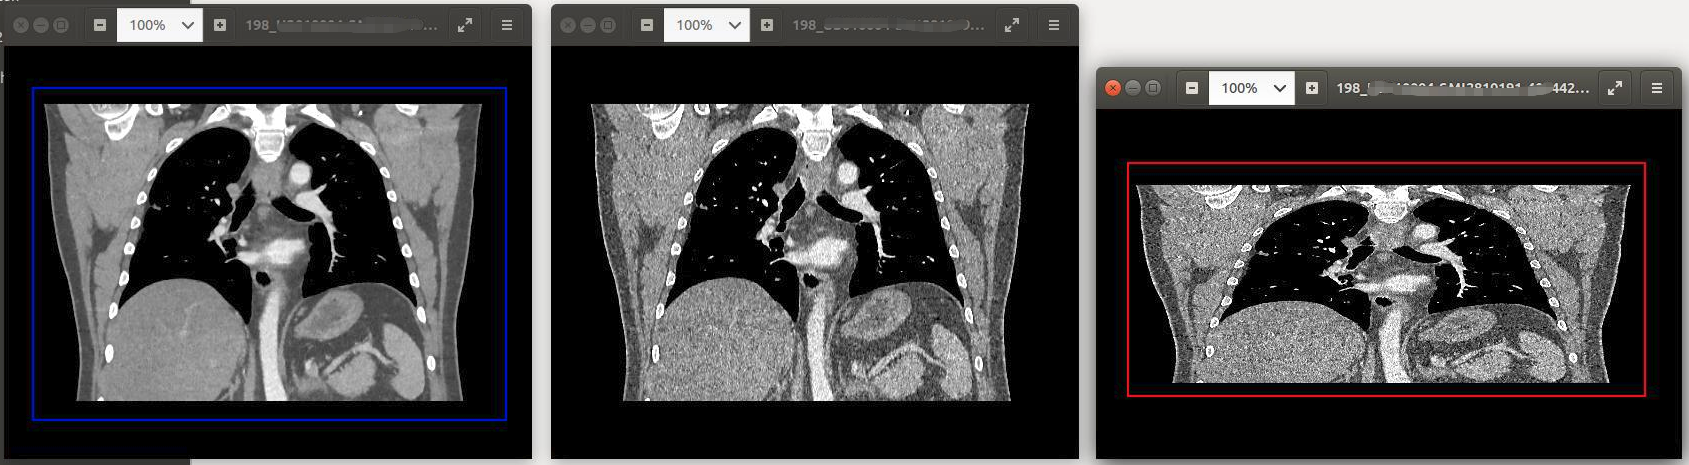

我们先来直观地看一下这三个轴状位的序列,生成的冠状位的缩略图的截图。

这三张缩略图,分别就是由西门子(SIEMENS CT)拍摄的这个检查的三个轴状位的序列生成的缩略图。这三个序列的张数都是198张,但是它们用同一套生成缩略图的代码,却生成出了三张完全不同的缩略图。而这是由它们所携带的一些tag信息和像素信息所决定的。

最终和公司的算法同事讨论,他们认为第一张缩略图代表的序列,更适合做肺结节的检测; 而第二张缩略图,则更适合做骨折等的检测。而第三张,它的缩略图比例都不太对,应该是有点问题的序列,是需要过滤掉的。